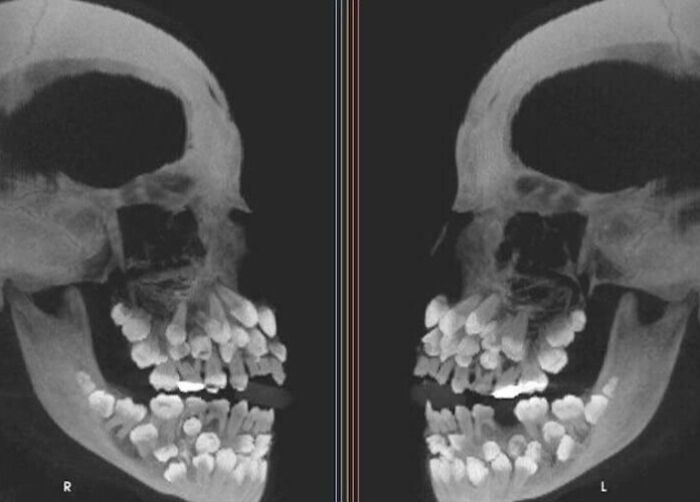

Una radiografía de una persona que tiene tres juegos completos de dientes

Es súper numerario. Mi marido también, tuvo un accidente de niño, perdió dientes q ya no eran de leche pero le volvieron a salir. La versión moderada es ese colmillo q sale por encima del q tienes.